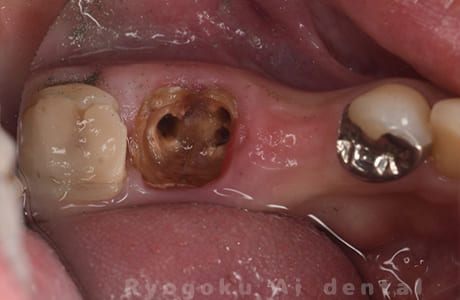

Case13

- 原因

- 歯根破折

-

- 治療内容

- インプラント治療

- 治療費用

- 約600,000円

奥歯が痛いとのことでご来院された患者様です。ブリッジ治療と共に相談し、インプラントをご選択されました。大変満足して頂けました。

<リスク・副作用>

治療後、痛みや違和感、出血、腫れなどが出る事があります。喫煙者、糖尿病などの方の場合、歯が生着しない場合があります。